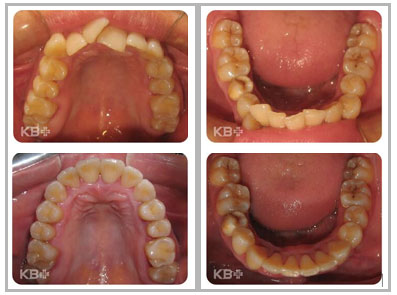

康贝佳口腔医院正畸科主任巴沙尔表示:牙列拥挤在错合畸形中较 为常见,分为单纯拥挤和复杂拥挤。

单纯拥挤表现为牙齿因间隙不足而排列错乱,并因此影响到牙弓形态与咬合关系;单纯拥挤可视为牙性错合,一般不伴颌骨及牙弓间关系不调,也少有口颌系统功能异常,磨牙关系中性,面形基本正常。

复杂拥挤时,除牙量不调造成的拥挤之外,还存在颌骨、牙弓间关系不调,并影响到患者的面形,有时还伴有口颌系统功能异常;复杂拥挤时拥挤本身只是一个症状,并不是错合的主要方面。